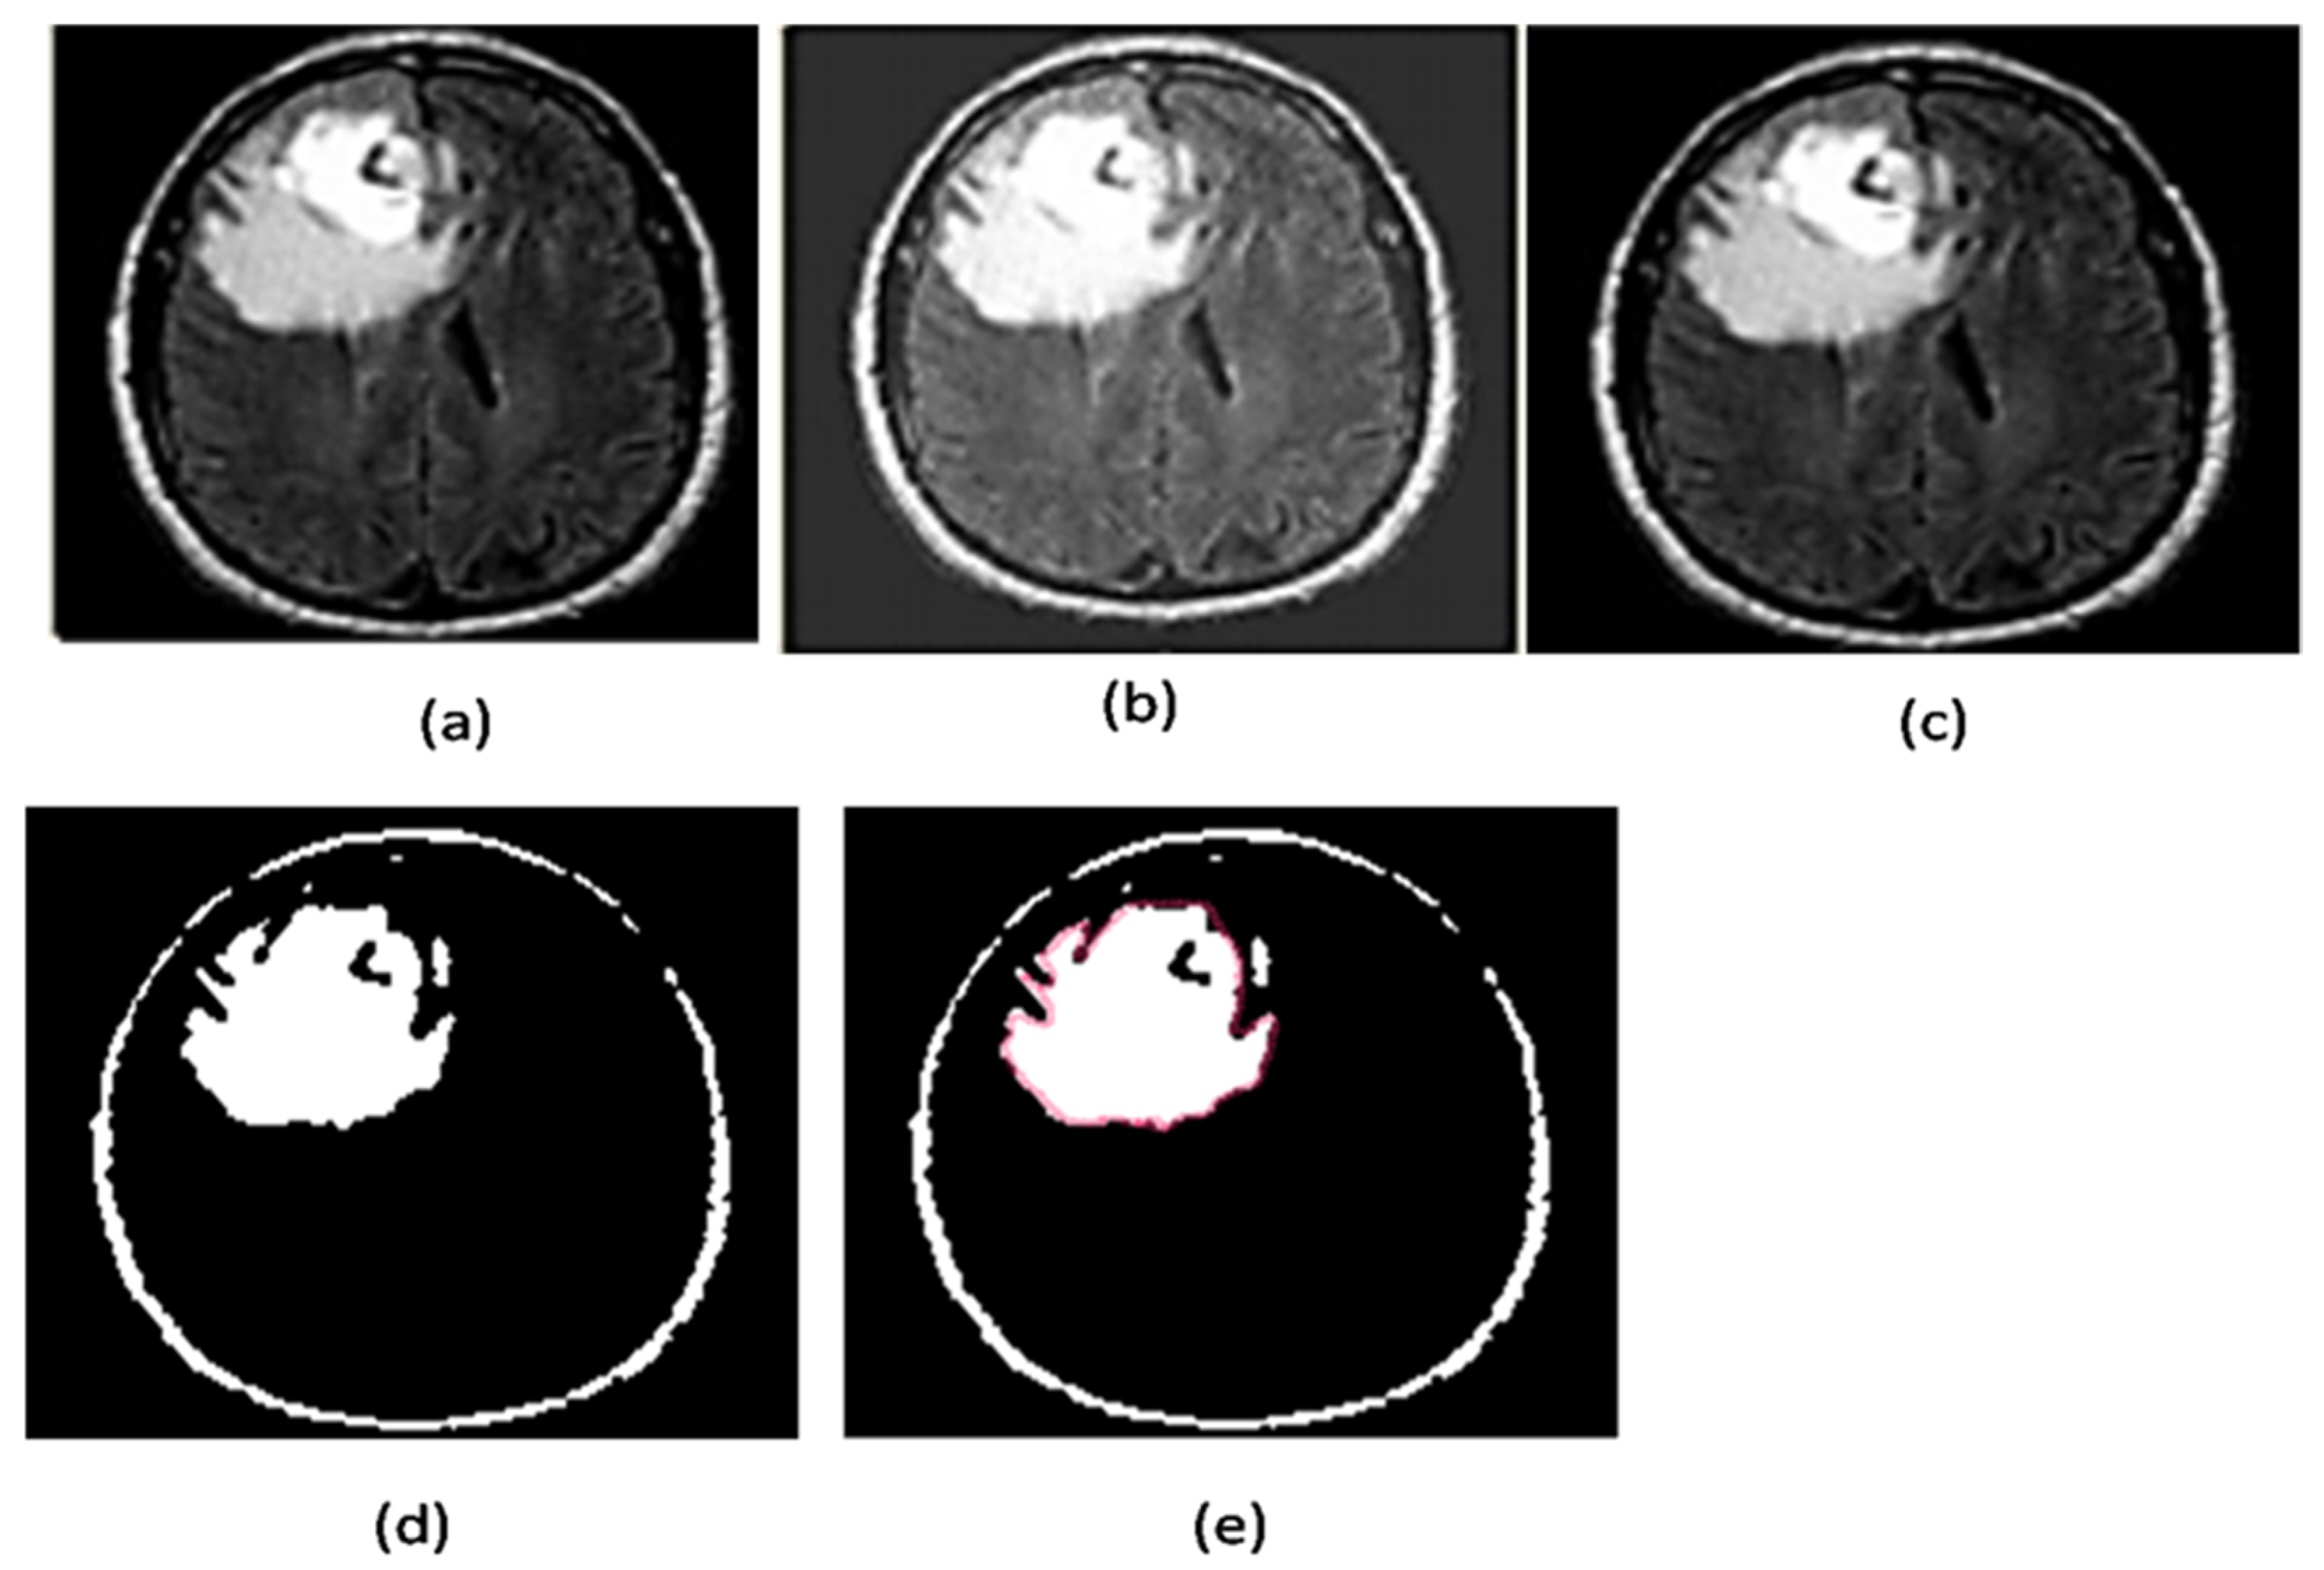

2.2.8. Region Masking and the Separation

2.3. Proposed a Colorized Method for Masked Area Colorization

3. Results and Discussion

3.2. Performance Evaluation